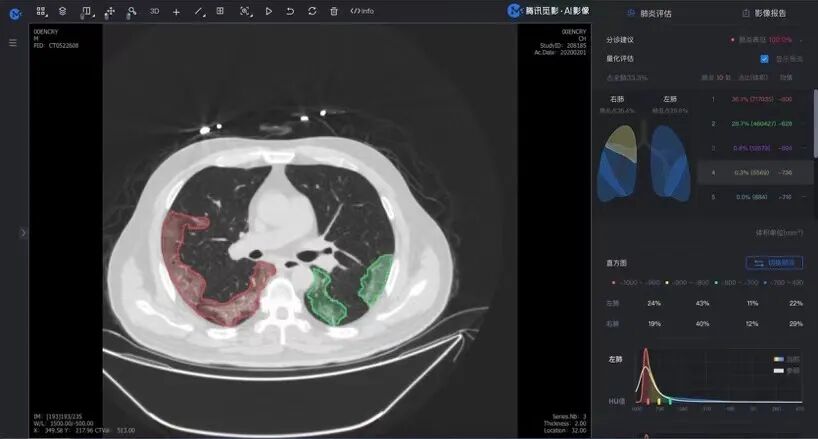

人工智能的智能辅助 则为医生诊断保驾护航,快速检出和判别疑似新冠肺炎,自动勾勒病灶,通过自动化的统计和直方图显示,为医生快速挑出需要重点审阅的疑点,第一时间进行准确的诊断。